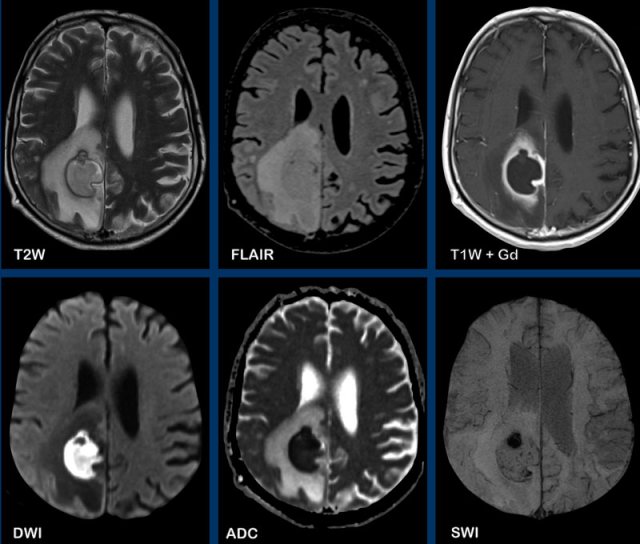

These images are of a patient, who presented with headache.

Images

There is a right parietal lesion, with rim enhancement and central diffusion

restriction.

SWI shows susceptibility at the rim, this is thought to be due to

paramagnetic free radicals, produced by macrophages.

There is also a

hemorrhagic spot at the ventral side, where diffusion is not restricted.

The faint enhancement

outside the inner rim, due to blood-brain-barriere leakage, can make

differentiation from a tumor difficult, but the restricted diffusion,

together with a low rCBV (not shown) makes the diagnosis of an abscess the most likely